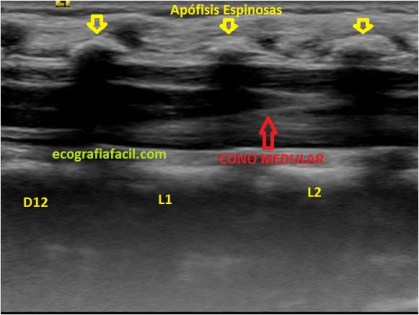

Colocaremos la sonda, para localizar en longitudinal el canal medular, debemos concretar a qué nivel termina el canal medular, para ello debemos saber cual es el nivel y las vértebras, para ello contaremos desde L5 hacia arriba.

Localizamos L5 estudiando el Sacro y contando desde la última espinosa lumbar y contando cuando identifiquemos L5, de ahí hacia craneal.

Imágenes desde distal hacia craneal, corte longitudinal.

Haremos cortes longitudinales y transversos e identificaremos D12, L1,L2 y L3 en Longitudinal.